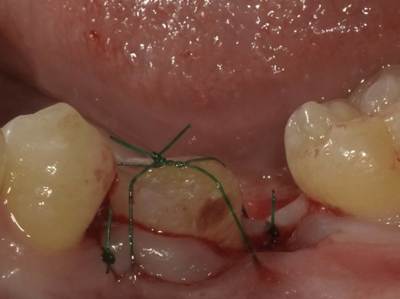

【症例 5】

左下8番を左上6番に移植